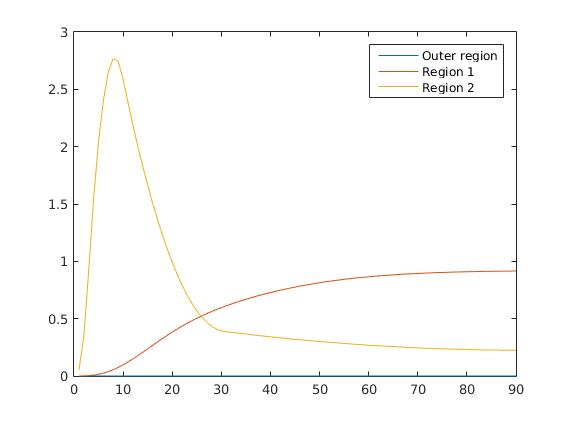

To test our reconstruction method, we created different synthesized data sets consisting of pixels with varying complexity of the image structure and with a different number of subregions and a total of 90 time steps in each sequence. Based on these subregions, we created three-dimensional matrices containing the true image in one time step within each slice. The underlying concentration in each subregion is related to a realistic shape of a the time-dependent behaviour of the tracer in different tissue types.

imaging, we used a synthesized representation of a rat liver as a second data set (see figure 1 (b)). The temporal concentration curves used to simulate the data sets

are shown in figure 2. As before, the total number of subregions was chosen to be equal to four in order to provide a both simple and realistic shape model.

5.2 Monte Carlo Simulation

In order to test the behaviour of the proposed method in a more realistic, random-based test case, we performed a Monte Carlo simulation for dynamic SPECT imaging. First, we created a simple image phantom consisting of an outer and two inner circles which represents the structure of the region of interest (see figure 8(a)). Within those regions we assumed concentration curves over a time period of 90 time steps as displayed in figure 8(b). Based on the tracer intensity in an image frame at each time step, we created a variable number of random decay events (where the number is proportional to the average concentration in one pixel in the whole image frame per time step) with a probability proportional to the concentration in every subregion. They are detected by a virtual double head gamma camera rotating around the patient by 46 degrees per time step, which consists of 374 detector bins. Every simulated decay event is projected onto the scanner and counted by the corresponding detector bin.